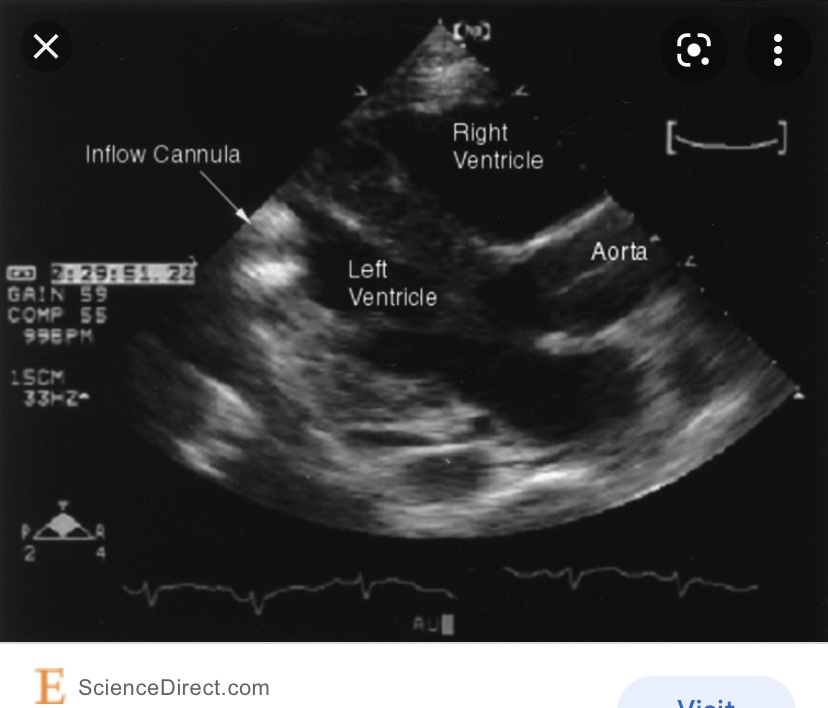

They consist of Inflow Cannula, Axial magnetic Rotor Pump and Cebtrifrugal propeller pump, outflow cannula (Aorta) and external battery (ASE).

It’s hard to take pictures of either LVAD due to patients body habitus, post surgical dressings, stitches and supine position. Also, the flow is continuous. But when doing echo on LVAD patient, make sure you annotate the type, mode and pump speed. Take LV dimentions and measure EF by Simpson’s. Take pictures of aortic valve and run m-mode with reduced speed to 50mm/s, record LVAD inflow from apical conduit and use color and pulsed Doppler. And record outflow into the ascending aorta with dolor and PW. Make sure you take images (if possible) of the right heart, record any TR, visualize and take color and PW Doppler of IVC. And use color if needed to rule out any thrombus formation.

Below are a few images and videos of RVAD and changes in RAMP study I did recently